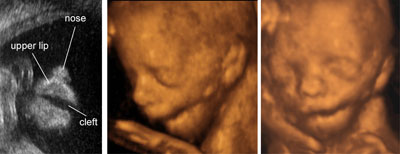

Varieties of fetal facial clefts

Legend:Varieties of fetal facial clefts

Isolated cleft lip

Legend:Isolated cleft lip

Cleft lip and palate

Legend:Cleft lip and palate